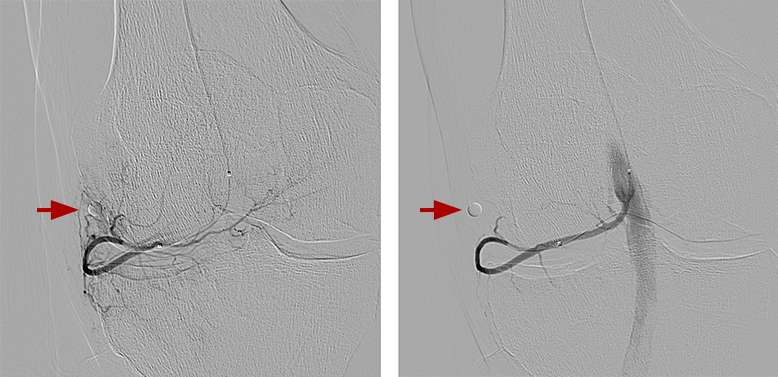

Initial (left) and final (right) angiograms of the knee after embolization. A circular marker was placed at the site of pain. The reduced blood-flow at the site of pain after embolization reduced inflammation of the knees.

GAE is performed with moderate ‘twilight’ sedation as an outpatient procedure, meaning the patient will go home after the procedure. The procedure generally takes one to two hours. Our IR physicians will insert a small catheter (a thin hollow tube) into the artery of the patient’s upper thigh and, with the use of X-rays, guide the catheter to the arteries supplying the lining of the knee. Tiny particles are then injected through the catheter into these arteries, reducing the blood supply. This in turn reduces the inflammation associated with osteoarthritis, which alleviates the pain.